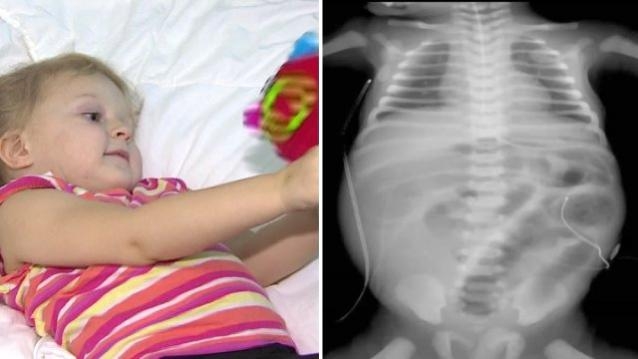

21 Ağustos 2025 Perşembe 21:38EŞİNİ MUAYENE EDEN DOKTOR, KIZI BABA, BENİ DE MUAYENE ET DEDİ, MUAYENE EDİNCE ŞOK OLDU Rahatsız edilen eşinin muayenesini yapan Ukraynalı doktor, kızının araya girip “Baba, beni de muayene et” talebindeni kıramadı. Yaptığınız kontrol sonucu kızının karnında tümörü tespit eden doktor davranışlarını şokunu yaşadı. Küçük kız, İstanbul'da başarılı bir ameliyatla sağlığına kavuştu. Devamını okumak için Lütfen sonraki sayfaya geçiniz..